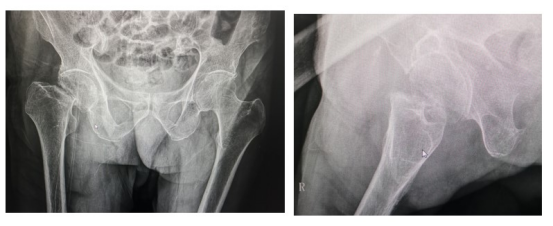

2022年2月24日,突如其来的意外使得邱金福老爷子失去了行走的能力,为求治疗,前往相关医院就诊,因患者年高,108岁,考虑到风险问题,所寻求医院拒绝为其进行治疗。最后辗转来到金瓶梅电影 ,来到金瓶梅电影 关节骨科后,由涂宏主任接诊并收入金瓶梅电影 行住院治疗。完善检查检验,影像学资料显示:右侧股骨颈骨折,符合手术指征。